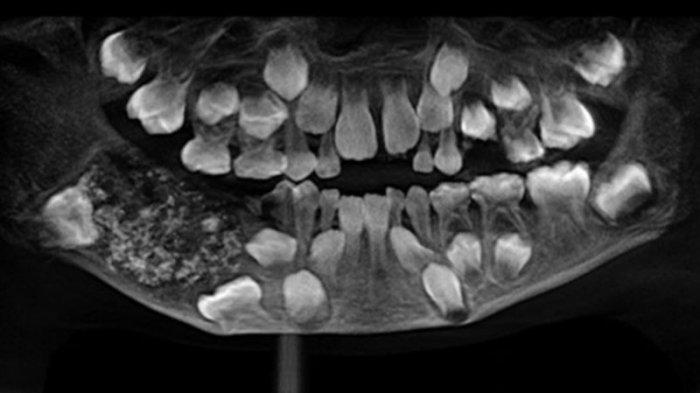

Tapi pada kenyataannya, di mulut anak 7 tahun tersebut, ditemukan 526 gigi saat difoto lalu dioperasi di sebuah rumah sakit di India.

Sebanyak 526 gigi dicabut dari mulut bocah 7 tahun oleh ahli bedah di India. (Saveetha Dental College and Hospital)

Hasil X-ray menunjukkan bahwa ada pertumbuhan seperti kantung yang tertanam di rahang bawahnya yang diisi dengan "gigi yang tidak normal".